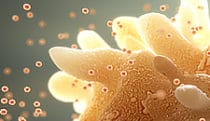

Engulfing pathogens

Work -